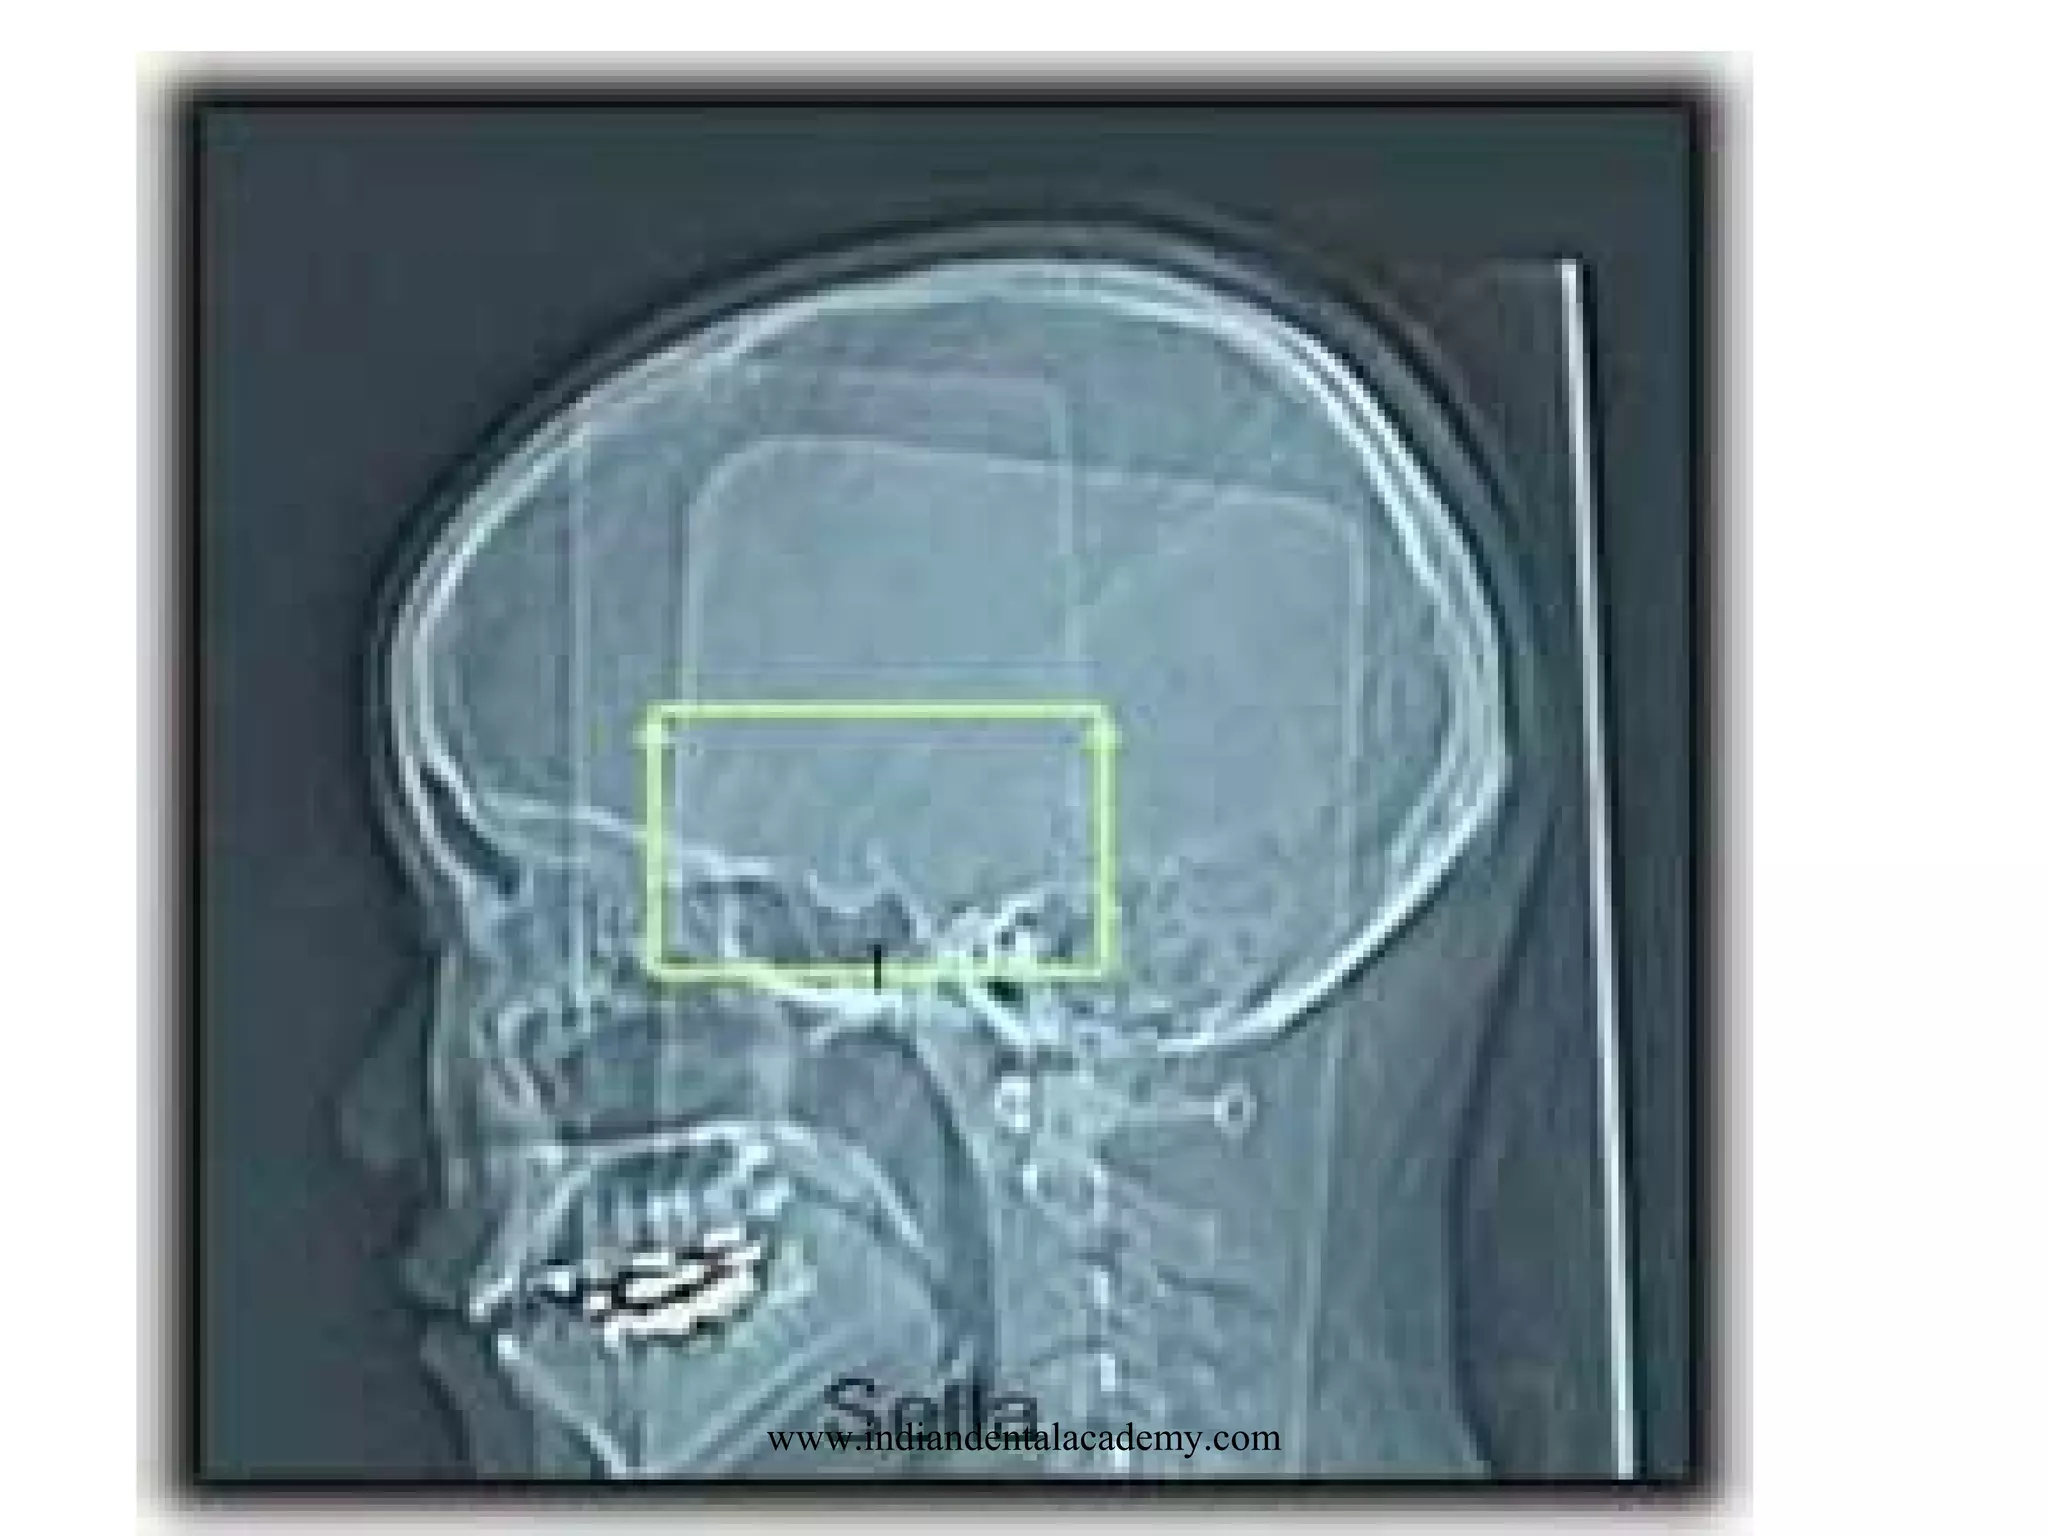

PITUITARY AND SELLA TURCICA

SCOUT: LATERAL

LANDMARK: OML

SLICE PLANE: CORONAL & AXIAL

I.V. CONTRAST: 100-140 ML

BREATH HOLD: NONE

SLICE THICKNESS: 1-1.5 mm

FILMING: BONE & SOFT TISSUE

www.indiandentalacademy.com

DFOV

12